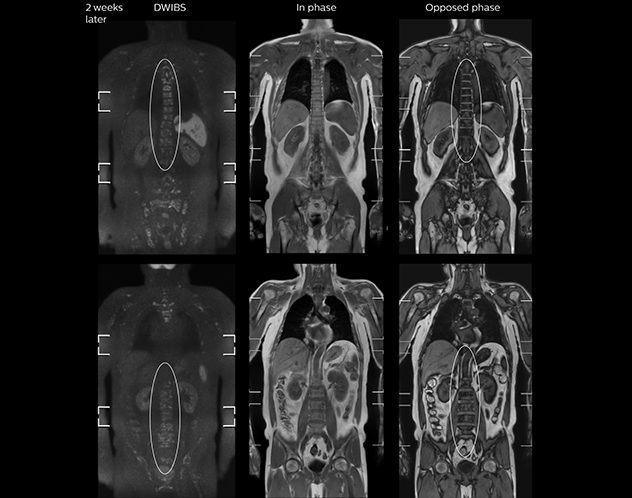

“In-phase and out-phase sagittal T1-weighted FFE images help us to visualize and further characterize bone lesions such as metastasis and bone-marrow hyperplasia that have high signal on DWI. These images are also used throughout radiotherapy, to monitor changes in the fatty bone marrow.”

After implementing the improved whole body protocol, the radiology team initially did not see a large increase in referrals, although Dr. Nobusawa saw clinical cases where the DWIBS images provided him valuable information for diagnosis. This is why Dr. Nobusawa and Mr. Naka started to actively educate referring physicians about the value of whole body DWIBS. They organized several presentations for physicians in the hospital, where they explained how DWIBS can be of value in oncology patients. The information it provides can be useful for physicians when staging cancer, as well as when determining or adjusting treatment strategy. Mr. Naka remembers some cases where DWIBS provided remarkable information. “In one example, DWIBS visualized bone lesions that could not be seen on PET or SPECT. In another case we had found a bone lesion when a normal L-spine scan for narrowing of the disk space was done. One extra DWIBS scan (2 stations, 8 minutes) demonstrated a lesion that later was confirmed to be the primary region of cancer.”

As oncologists and surgeons have learned more about DWIBS, referrals for the exams have increased. In 2015, the 326-bed hospital’s radiology department doubled their number of whole body DWIBS exams compared to 2014.

In certain cases, radiologists now choose DWIBS to make diagnoses that used to depend on nuclear medicine studies. “We don’t have SPECT or PET in our hospital, so for instance for visualizing metastasis and monitoring the effect of treatments such as chemotherapy or radiotherapy, we used to refer patients outside the hospital. Now, these patients are sent to MRI for our whole body protocol with DWIBS,” Mr. Naka says.